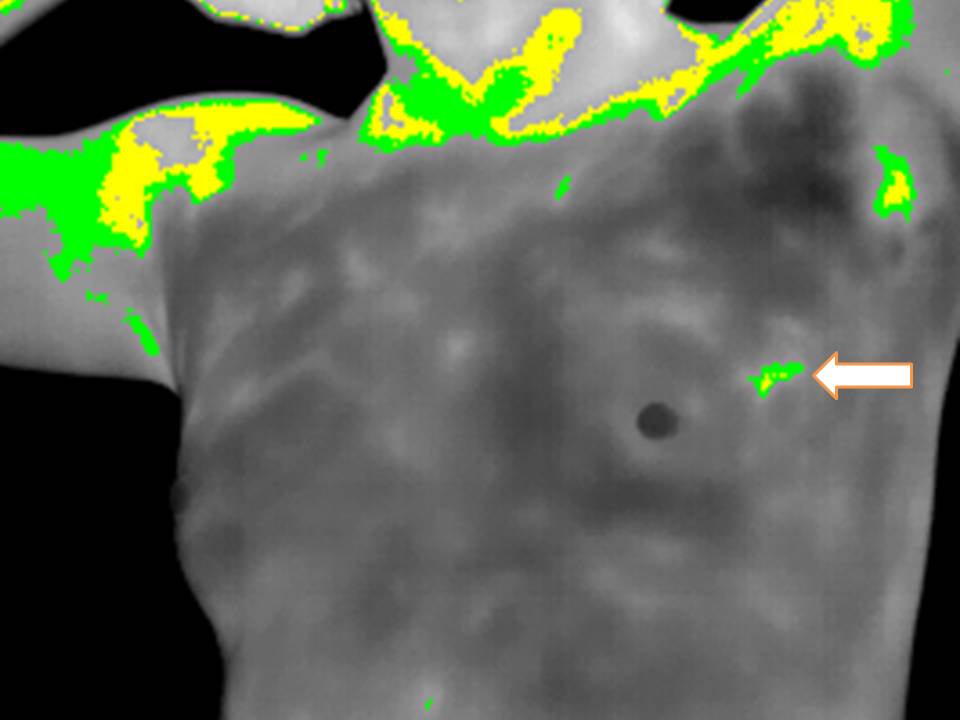

Infrared Analysis of the Anatomical Region. Clear Differences in Color are seen as Infrared Radiation Rises. Advanced and current State of the art IR detectors have a LARGER color scale, resolution and pixels.

Software Color and Palette options can can choose only gray scale , white and black:

And with the Use of Automatic "ISTOTHERMS" or color ranges , the highest IR radiation areas are limited and subsecuently could be measured.

Software manipulation and applications can give objective numerical reproductible results and hence record them and compare if future instances occur.

Angiogenesis in Angiosarcoma is EVIDENT , local heat is risen because of VASCULAR DENSITY and in part I assume could explain what happens in SOME TYPES of Breast Cancer.